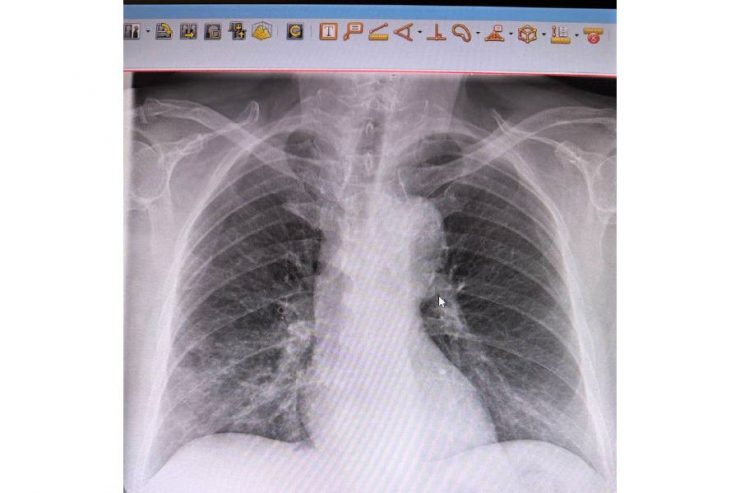

Бригада скорой доставила пациента в в реанимационное отделение Центральной городской больницы с анафилактическим шоком, отеком Квинке и давлением 80/50. Врачи стабилизировали его состояние лишь через сутки. Обследование выявило ещё и пневмонию. Сейчас мужчина переведён в пульмонологическое отделение, его жизни ничего не угрожает.